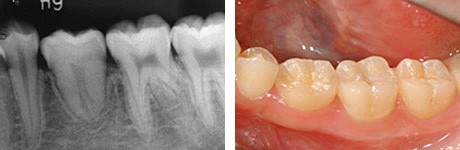

左:移植直後のエックス線写真。

右:移植後1ヶ月。